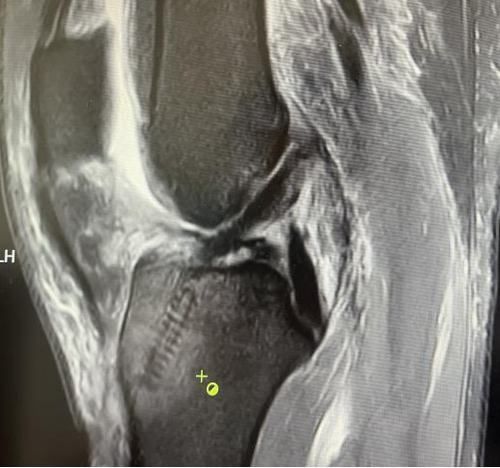

術后磁共振

我院骨科三病區近期收治了4名膝關節交叉韌帶損傷患者。25歲的齊先生,因打籃球時不慎扭傷左膝,致右膝腫痛,遂來我院治療;30歲趙先生酷愛足球,扭傷右膝關節來我院就診;50歲的張先生、42歲劉先生因騎車滑倒摔傷、膝關節腫痛不適、活動受限,收治入院。骨科三病區李鵬主任團隊詳細查體以及完善影像學檢查后進行診斷:幾位患者共同診斷均有“前交叉韌帶損傷”,不同程度合并有“半月板損傷”、“股骨軟骨損傷”、“內側副韌帶斷裂”。

經患者同意后,李鵬主任手術團隊制定詳細手術方案。手術如期進行,經團隊密切配合,對幾位患者分別順利完成關節鏡下膝關節鏡鏡檢、關節清理、股薄肌半腱肌取腱移植術、前交叉韌帶重建術、軟骨損傷微骨折術、半月板縫合修整術等。